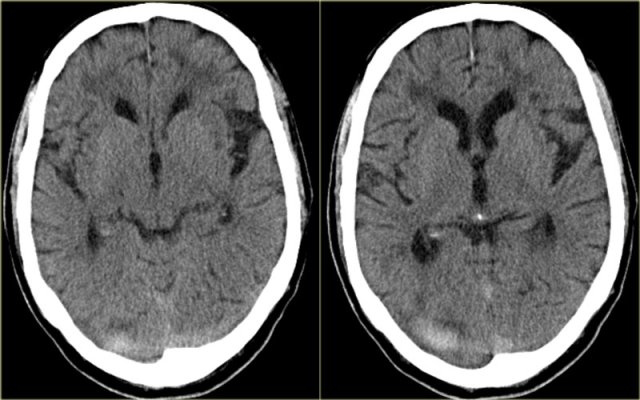

Venous infarction (2) - Superior sagittal sinus thrombosis

The most frequently thrombosed venous structure is the superior sagittal sinus.

Infarction is seen in 75% of cases.

The abnormalities are parasagittal and frequently bilateral.

Hemorrhage is seen in 60% of the cases.

On the left bilateral parasagittal edema and subte hemorrhage in a patient with thrombosis of the superior sagittal sinus.

On the left reconstructed sagittal CT-images in a patient with bilateral parasagittal hemorrhage due to thrombosis of the superior sagittal sinus.

The red arrow on the contrast enhanced image indicates the filling defect caused by the thrombus.